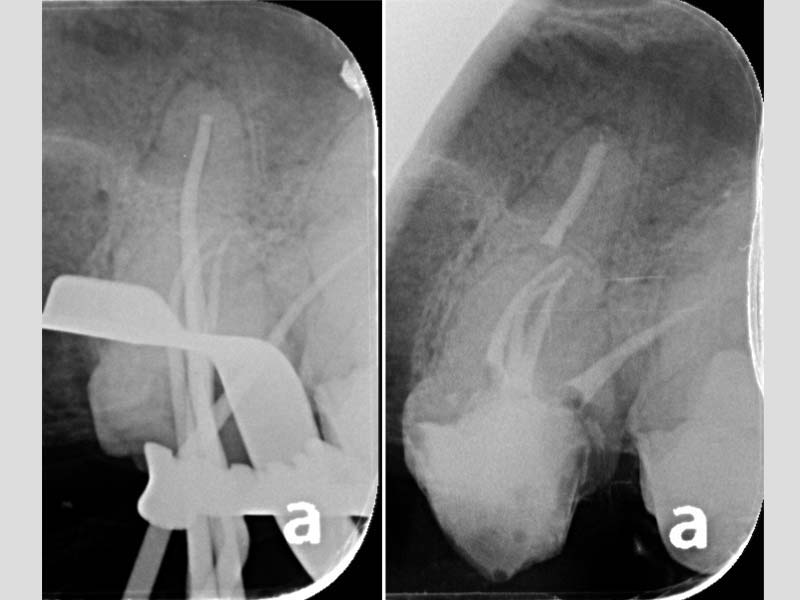

治療前X光:診斷左上顎最後三尺為均需要根管治療

左上顎第二小臼齒:顯微鏡下確診牙裂,建議拔除

左上顎第一大臼齒:為五根管的難症(罕見變異多根根管)

左上顎第二大臼齒:也是五根管的難症(罕見變異多根根管)

治療後X光